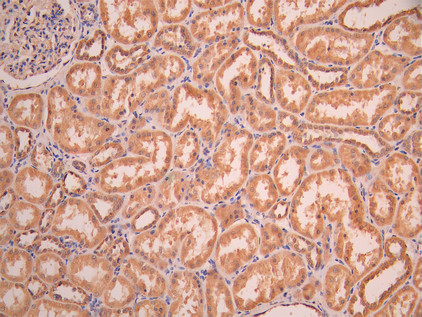

• IHC image of CSB-RA283972A0HU diluted at 1:100 and staining in paraffin-embedded human kidney tissue performed on a Leica BondTM system. After dewaxing and hydration, antigen retrieval was mediated by high pressure in a citrate buffer (pH 6.0). Section was blocked with 10% normal goat serum 30min at RT. Then primary antibody (1% BSA) was incubated at 4°C overnight. The primary is detected by a Goat anti-rabbit polymer IgG labeled by HRP and visualized using 0.05% DAB.